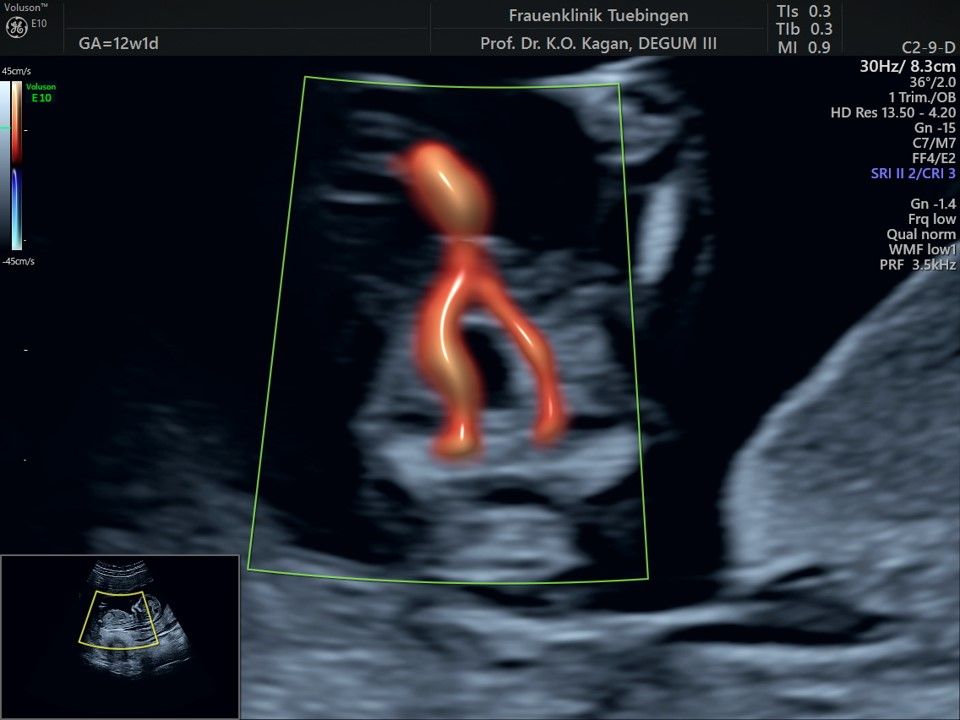

Das Ergebnis der Ultraschalluntersuchung ist wegweisend. Dabei wird der Fet vermessen, die Organe werden untersucht und die sonographischen Marker zur Risikoberechnung für Chromosomenstörungen werden beurteilt. Das sind: die Nackentransparenzdicke, Nasenbein sowie der Blutfluss in der rechten Herzhälfte und im Ductus venosus, einem Gefäß in der Leber des Feten.

Mithilfe des Ersttrimester-Screenings kann das persönliche Risiko einer Präeklampsie bestimmt werden. Dazu wird die Vorgeschichte der Schwangeren, der aktuelle Blutdruck, das Ergebnis der Ultraschalluntersuchung (Widerstand in den Gebärmutter-nahen Gefäßen) und der Blutabnahme bei Ihnen (PAPP-A) kombiniert. Sollte das Risiko über 1:100 sein, empfehlen wir die tägliche Einnahme von Aspirin 150mg bis zu 35.SSW und eine gezielte Überwachung der weiteren Schwangerschaft.